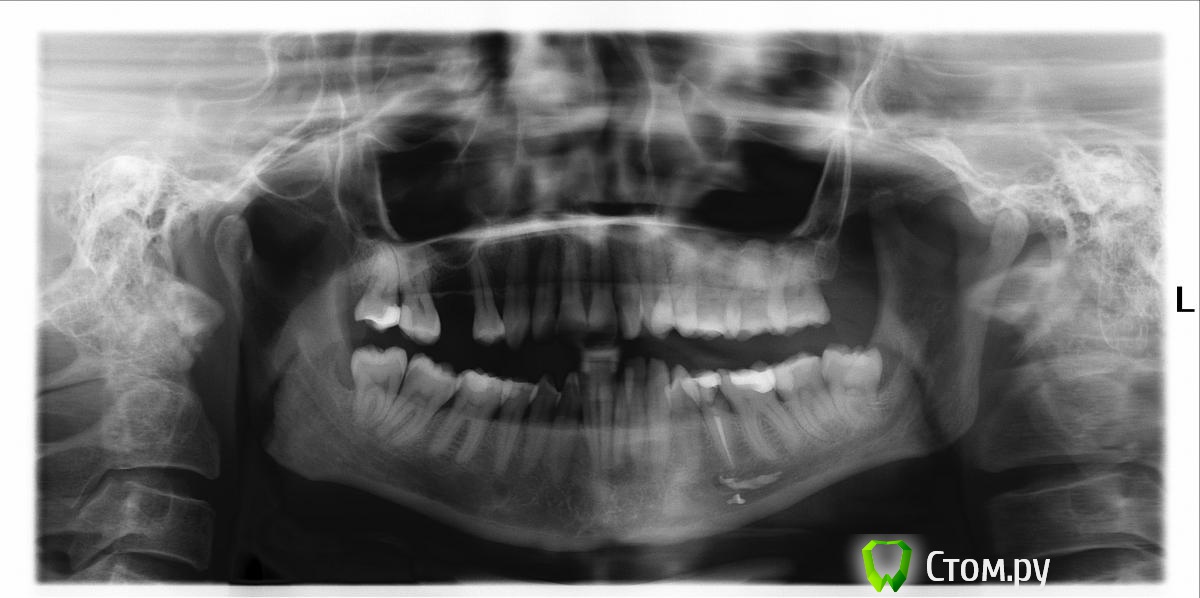

Bratok Опубликовано 13 сентября, 2014 Поделиться Опубликовано 13 сентября, 2014 (изменено) Вот вам в тему эндосвалки Изменено 13 сентября, 2014 пользователем Bratok Ссылка на комментарий

Stomart Опубликовано 13 сентября, 2014 Поделиться Опубликовано 13 сентября, 2014 (изменено) Как думаете, 6ку лучше сразу выдернуть или все-таки залезть и посмотреть? Смущает какой-то процесс между корнями. Планируется мост, но если удалять, то мосту уже не быть. Я бы залез ради интереса и глянул на дно пульповой. Вот вам в тему эндосвалки Это лучше в тему про врачей-водителей трамваев. Изменено 13 сентября, 2014 пользователем Stomart Ссылка на комментарий

Kolchanov Опубликовано 13 сентября, 2014 Автор Поделиться Опубликовано 13 сентября, 2014 Вот вам в тему эндосвалки Ну, что, ничего необычного. Левый случай поправим, в правом же, если симптоматики нет, то и фиг с ним. Ссылка на комментарий

Bratok Опубликовано 13 сентября, 2014 Поделиться Опубликовано 13 сентября, 2014 (изменено) Ну, что, ничего необычного. Левый случай поправим, в правом же, если симптоматики нет, то и фиг с ним. Это снимок женщины 40 лет, с момента пломбировки прошло 6 лет. Жалобы на отсутствие чувствительности нижней губы слева, части подбородка.. Как ей помочь? Стационар? Изменено 13 сентября, 2014 пользователем Bratok Ссылка на комментарий

Kolchanov Опубликовано 13 сентября, 2014 Автор Поделиться Опубликовано 13 сентября, 2014 Никак. Ссылка на комментарий

Slaggy Опубликовано 13 сентября, 2014 Поделиться Опубликовано 13 сентября, 2014 (изменено) Это снимок женщины 40 лет, с момента пломбировки прошло 6 лет. Жалобы на отсутствие чувствительности нижней губы слева, части подбородка.. Как ей помочь? Стационар? Бедненькая, как же она целуется? Если согласится - то стационар. Если хирург реально гламурен.6 лет срок, но человеческий организм врачи не смогли победить уже несколько тысяч лет. Выживает несмотря на наши старания.На все воля творца. А от операции хуже уже не станет. Лишь бы не резорцинка.Хотя и с ней выживают.Каюсь, был за мной такой косяк когда-то - через год восстановилась чувствительность. А я кроме эмоциональной накачки и массажа ничего тогда и не придумал. Изменено 13 сентября, 2014 пользователем Slaggy Ссылка на комментарий

krasnyi Опубликовано 15 сентября, 2014 Поделиться Опубликовано 15 сентября, 2014 Это снимок женщины 40 лет, с момента пломбировки прошло 6 лет. Жалобы на отсутствие чувствительности нижней губы слева, части подбородка.. Как ей помочь? Стационар?Однозначно - хир.стом.вмешательство. Мое мнение. Ссылка на комментарий

_omega- Опубликовано 17 сентября, 2014 Поделиться Опубликовано 17 сентября, 2014 Вот вам в тему эндосвалки это надо же... Печаль! Ссылка на комментарий